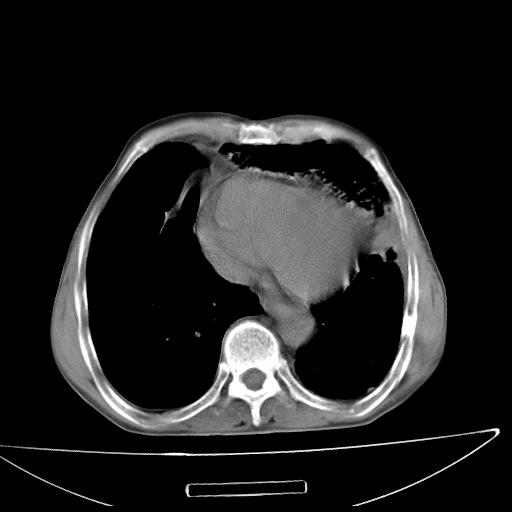

男  70岁,发烧咳嗽4天。盗汗,消瘦。无痰中带血丝,以前有肺tb病史,ct见,双肺tb,左侧胸廓塌陷,左胸膜肥厚粘连。纵隔移位,右侧胸腔积液,大家说说那个心影前左肺舌叶除了肺大炮还有炎症还是干酪性肺炎?有占位吗?我看纵隔淋巴结也大。

1)两肺继发性肺结核并左肺上叶肺不张,支气管扩张。2)双侧胸膜炎(胸膜增厚+少量胸腔积液)。

两肺继发性肺结核并感染,左肺上叶肺不张。建议ct增强。